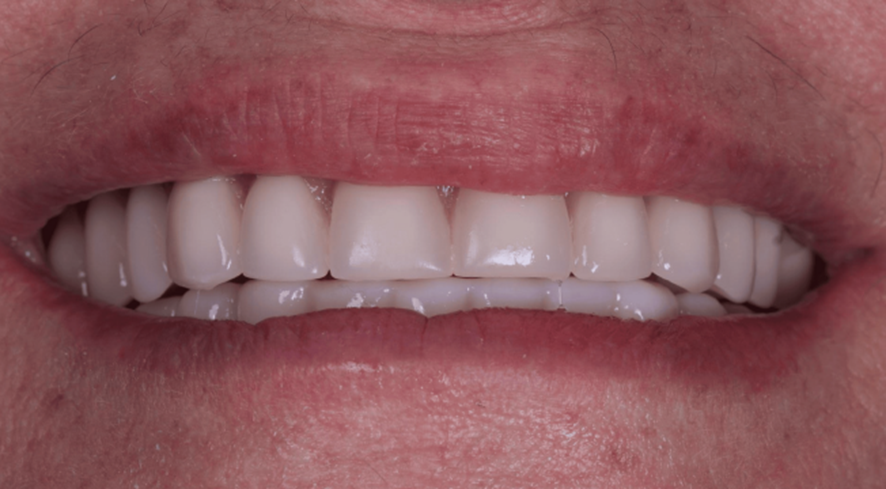

Em destaque na Matéria da Semana, apresentamos um caso clínico que envolve osteotomia, colocação de implante com carga imediata e cirurgia guiada e a instalação de uma prótese híbrida de resina impressa em 3D.

Dessa forma, esses elementos combinados com a execução cirúrgica e protética precisa, contribuem para o sucesso previsível dos protocolos de carga imediata na reabilitação mandibular de arco completo.

A novidade neste caso envolveu o uso de fluxo de trabalho digital, um guia cirúrgico empilhável personalizado de três partes e uma prótese provisória impressa feita de resina.